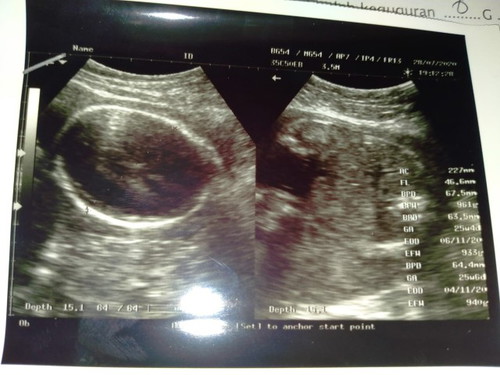

Bunda usia kandungan saya sudah 9 bulan. Pinggang sudah malai pegal pegal. Miss v nyeri sampai pantat , kemarin juga tiba2 mual. Keluar keputihan putih susu tp gak bnyak cuma sedikit. Perut nyeri bagian bawah kayak mau mens. Itu tandanya apa ya bunda apakah mau mendekati persalinan? #seriusnanya #bantusharing